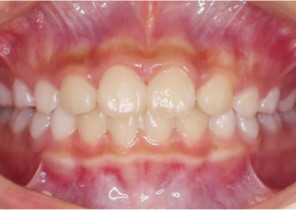

Pre Invisalign Palatal Expander Expansion

Post Invisalign Palatal Expander Expansion

After Invisalign First treatment